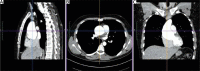

The main goal of minimally invasive surgery is to reduce the perioperative trauma, accelerate patient mobilization and reduce the length of hospital stay. Due to the development of modern technology, these treatments can be offered to a wider group of patients. For many years, aortic root surgery consisted of mechanical conduit implantation and, therefore, necessitated life-long anticoagulation. At present, in patients with aortic root aneurysm and significant aortic valve regurgitation, it is possible to perform minimal-access valve sparing surgical procedures. The current paper is a brief description of the surgical technique for aortic root aneurysm surgery with preservation of the patient's own valve using the David procedure.